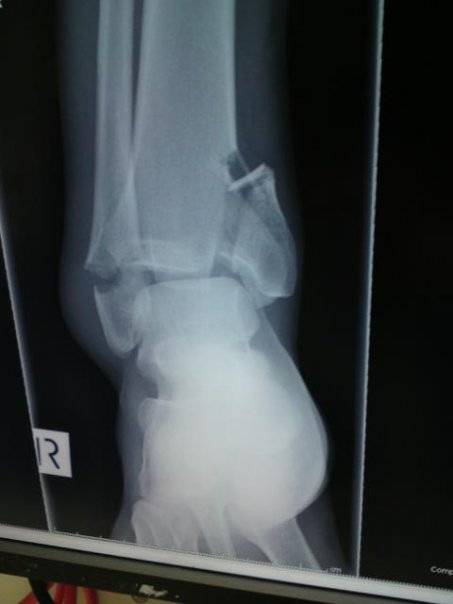

End result, dislocated ankle, multiple breaks then 3 days drugged to my eyeballs with nil to mouth and having to fight tooth and nail for a drip and morphene while waiting for 4 hours of surgery.

Sounds horrible. I'd frame those xrays and put em on the wall. When people come to your house you can say "hey, do you want to see photos from me kiting?", and you can point them to the screws in your bones.

Youve got to smile at the second xray though...

Looks like they gave you a random screw!

Reminds me of any carpentry job i ever did - ok now its fixed together tidily.. belt in one more screw for good measure! :)

Heres to a quick recovery mate. My own experience with titanium screws and plates was top job and speedy recovery.